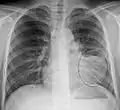

Left upper lobe pneumonia with a small pleural effusion.

Right lower lobe pneumonia as seen on a lateral CXR